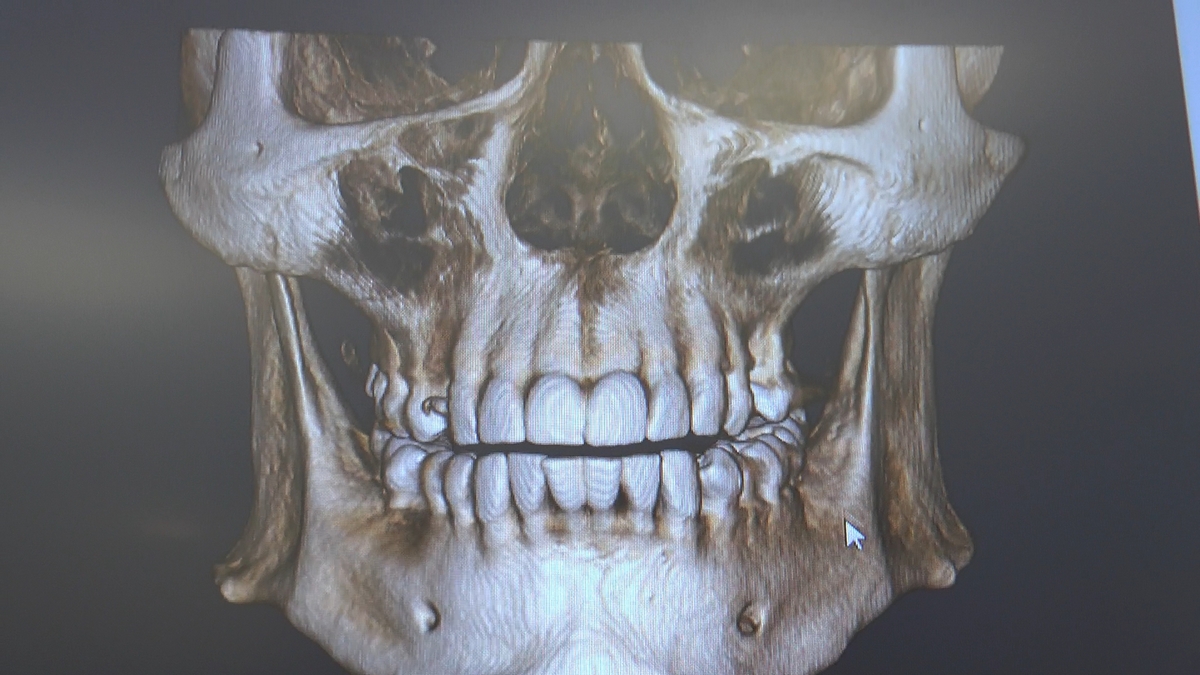

W trakcje dwóch dni zabiegowych, piątek i sobota, 5 i 6 października 2018 roku, lekarze uczestniczący w 6 Sesji VI Sezonu, wykonali wiele zabiegów o wysokim stopniu trudności. Przeprowadzili je pod kierunkiem Mentorów Instytutu Vivadental – dr n.med. Violetty Szycik, dr n.med. Magdaleny Kisłowskiej-Syryczyńskiej oraz dr Małgorzaty Piotrowskiej.

Wprowadziliśmy łącznie 25 implantów w tym wykonaliśmy:

dwa zabiegi All- on -4 / jeden w szczęce, jeden w żuchwie/ z usunięciem zębów i natychmiastową implantacją oraz natychmiastową odbudową protetyczną